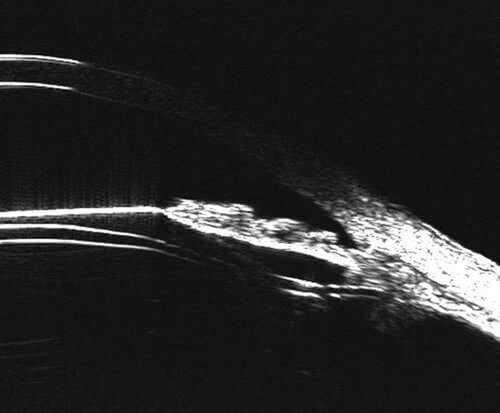

As you plan for and review pIOL surgery, zeroing in on the sizing and anatomy behind the iris leads to outcomes success. The Insight 100 pIOL Scan Sets capture anatomy that is easily measured using the Rapid Caliper Tool. With the data you gather, nomogram results are demonstrably more precise than the traditional sulcus-to-sulcus measurement.1 With further interpretation, you can identify pathologies or anatomical challenges to make surgical planning more comprehensive.

By employing the Insight 100 and its behind-the-iris ultrasound imaging, you and your patients can count on the precision and repeatability to prepare for and measure the outcomes of pIOL surgery.1

Anatomy and Artifacts

The Insight 100 Anterior Scan is comprised of tailored meridians, with very-high-frequency ultrasound multiple sweeps to deliver images that helps Ophthalmologists focus on elements like:

- Scleral spur

- Anterior chamber

- Ciliary body

- Masses and cysts

- Irido-corneal angle

- And more